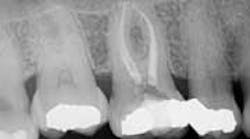

Radiographic interpretation showed the maxillary sinus, which appeared to be superimposed over the apex of teeth Nos. 2 through 4. In the radiograph No. 2 showed a shallow occlusal radiopaque restoration consistent with the appearance of amalgam. The mesial aspect of the tooth was visible with the mesiobuccal root showing. A radiopaque structure appeared to be within the chamber consistent with the appearance of a pulp stone. An apparent widening of the PDL at the apex of the tooth was visible. Tooth No. 3 showed a radiopaque MO restoration within 2 mm of the pulp chamber. The tooth appeared to exhibit three roots with the distal root appearing to be “bulbous” in presentation, and multiple periodontal ligaments were visible and associated with this root. The presentation of multiple periodontal ligaments is an indicator that multiple canals may be present within a root (Beatty). No. 4 showed a DO radiopaque restoration consistent with the appearance of amalgam; the canal space was visible to the junction of the middle/apical third in which it became obscure. The distal root aspect of tooth No. 5 appeared to be partially visible. (Fig. 1)Fig. 1: PA of maxillary posterior